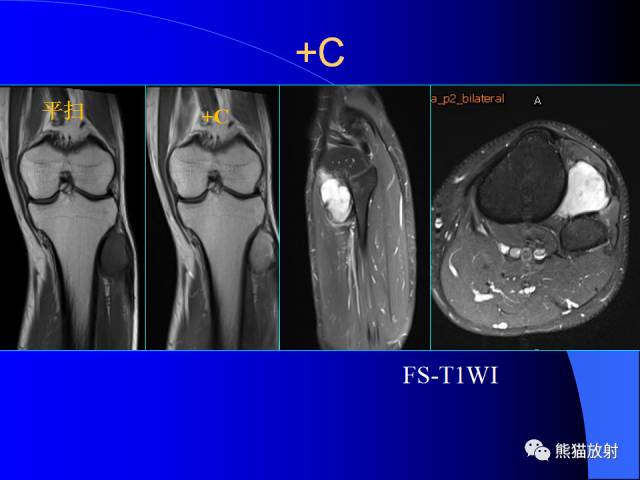

膝关节周围囊肿MRI

膝关节周围囊肿是较常见的病变,可以是原发的,多见于青年及儿童,囊内容物通常是黏液;也可以是继发的,多与关节腔相通,内含一般黏性的滑液,常继发于膝关节骨关节炎、类风湿关节炎、非特异性滑膜炎、半月板损伤、髌骨软骨软化症等。

腘窝囊肿是膝关节周围最常见的囊肿。